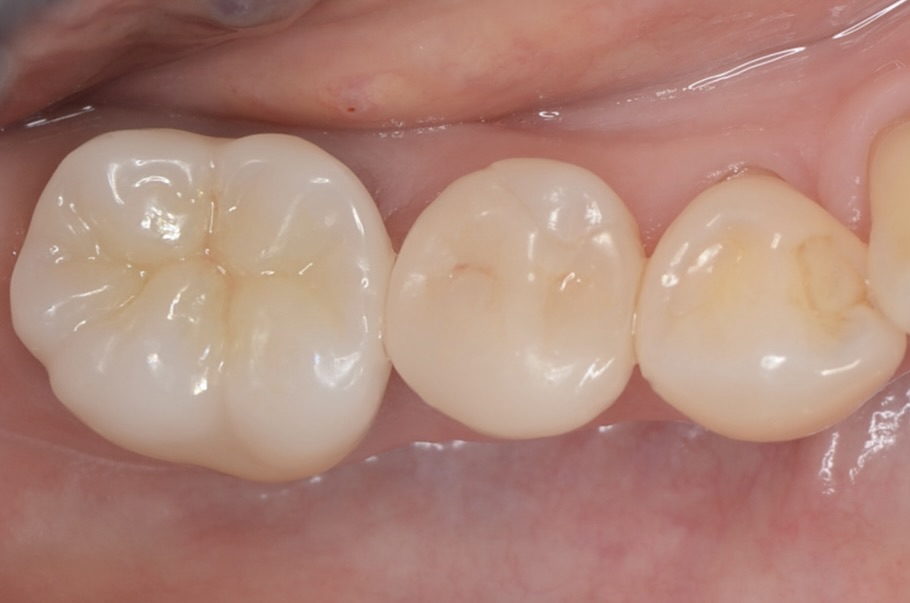

術後6ヶ月

歯肉は安定しました。ここから印象します。 -

ジルコニアクラウン

綺麗に補綴できました。 -